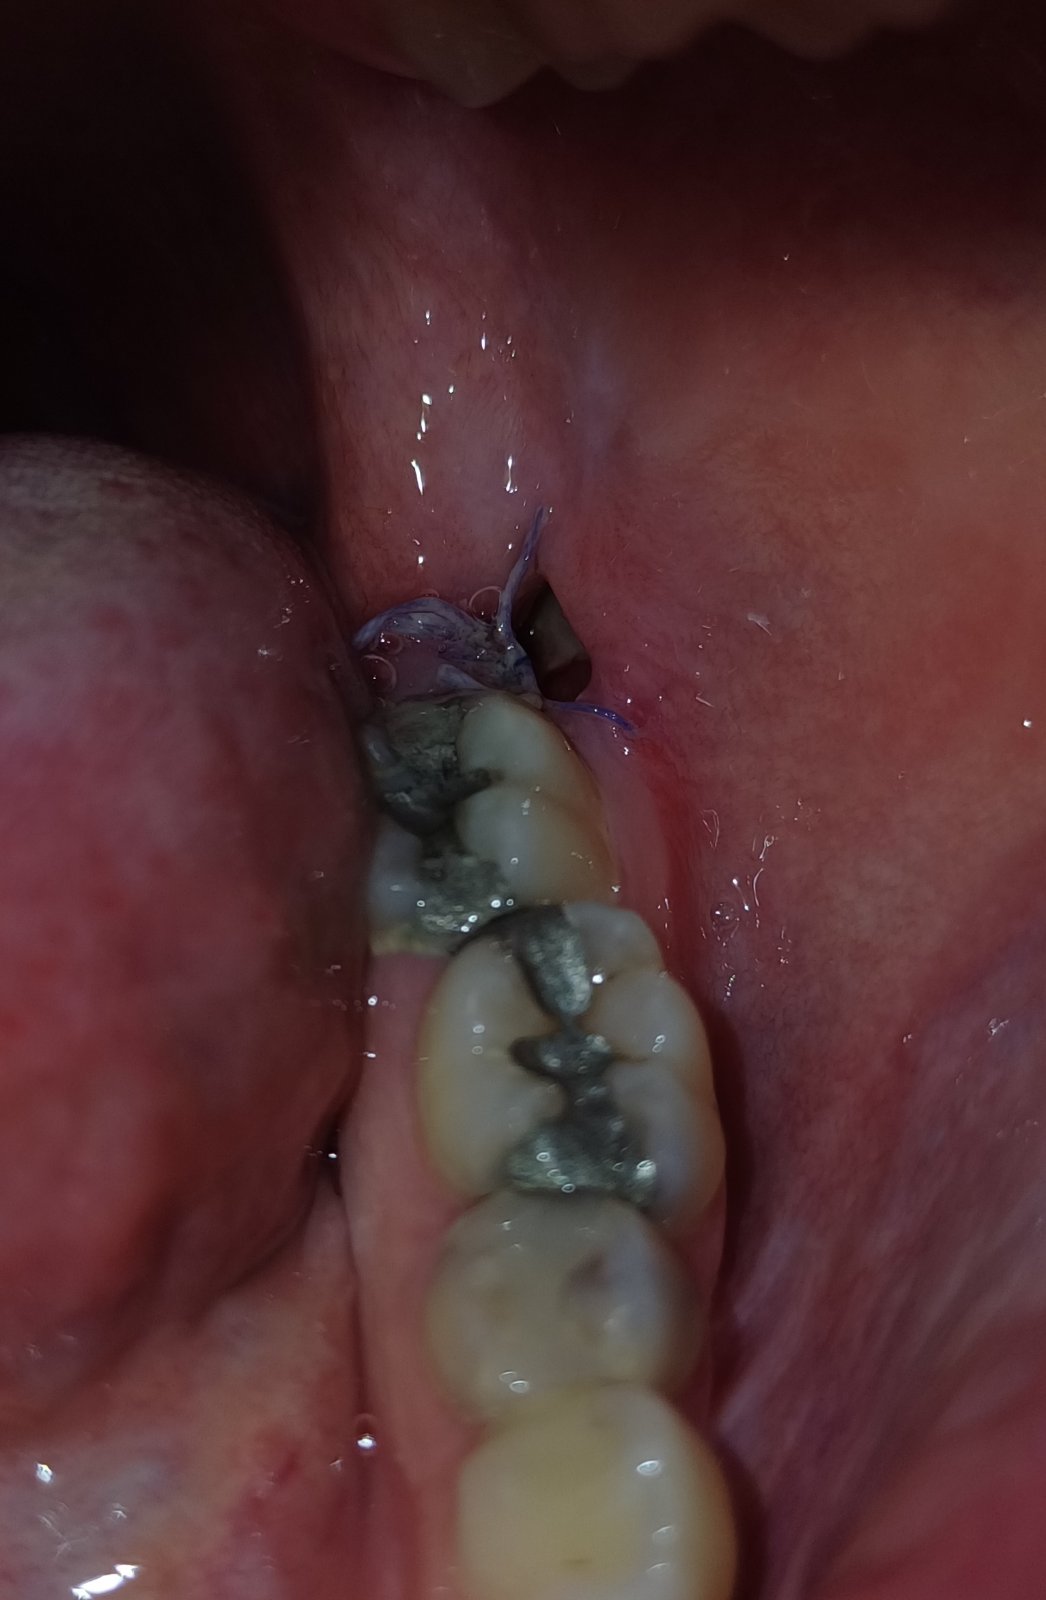

Ahojte,mal niekto rovnaky problem? O 2 dni budu 2 tyzdne odkedy mi tahali osmicku. Bol to pomerne tazky zakrok, mam to aj zasite pricom sa mi stehy uz rozpadavaju a rana otvara. Ako dlho vam trvalo kym sa rozpadli cele stehy? Tiez som si vsimla v rane nieco svetle(neviem ci to moze byt suche lozko?..alebo som len paranoidna). Casto sa mi tam zasekava jedlo ktore sa snazim opatrne vyberat. Rana ma vyslovene neboli. Samozrejme trochu ano,nakolko to bol tazky zakrok ale nie je to nic strasne na nevydrzanie, neberiem na to ani lieky. Predpokladam ze je to bezna bolest po extrakcii. Rozumie sa niekto do toho? Je to v pohode hojenie?

Úplne normálne hojenie, to biele je chrasta len zbavená farby v dôsledku slín, čo je úplne normálne, a stehy ak sú vstrebatelne asi tak do mesiaca sa rozpadnu. Ale ak dávali normálne treba ich vybrať. Sú pacienti ktorým vadia aj vstrebatelne a nechávajú si ich vybrať. Bolesť po trhani je normálna. A nesparat sa v tom zbytočne, jest na druhej strane a po jedle vyplqchnut ústa vodou čistou. A len kefkou umývať zuby a tam opatrne aby sa tá chrasta nedala prec.